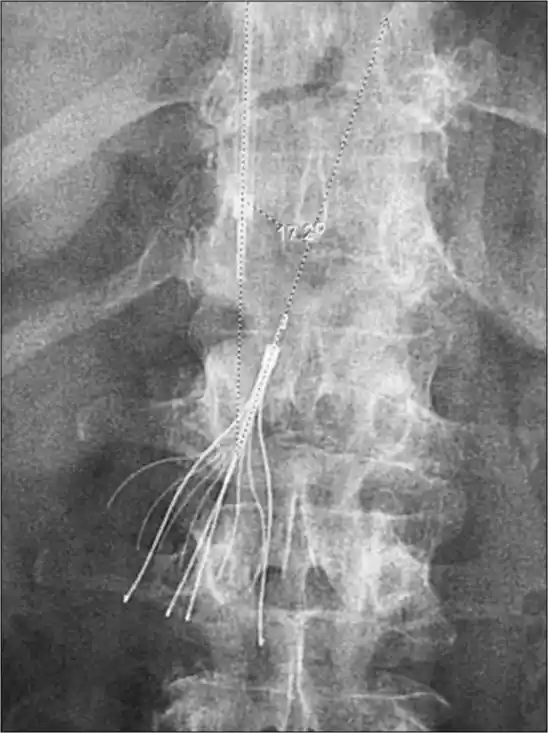

An umbrella-shaped device made of metal, the inferior vena cava filter is deployed through neck veins or groin using fluoroscopy. Its filtration mechanism intercepts large clots before they reach the heart or arteries of the lung. Interventional radiologists use image guidance to position the IVC device inside the large vein of the abdomen. Injectable anticoagulants and oral anticoagulants remain the standard treatment, but when anticoagulation fails, mechanical thrombectomy or catheter directed thrombolysis becomes necessary.

Contrast material confirms precise placement via fluoroscopy, allowing the IVC filter to expand against the walls of the blood vessel.

The filter is carefully deployed inside the inferior vena cava, trapping dangerous blood clots before they reach the heart or lungs.